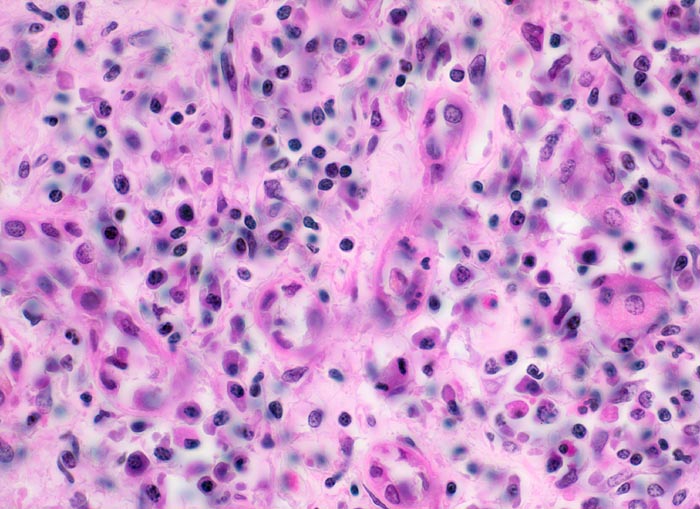

Polyarteritis nodosa Makroform: tubulointerstitielle Entzündung

Der tubulointerstitielle Raum ist ödematös aufgelockert und zeigt ein gemischtes Infiltrat aus Plasmazellen, Lymphozyten, Histiozyten und vereinzelten eosinophilen Granulozyten.

Makroskopischer Befund der Nieren: Vergrösserte Nieren mit Petechien und mehreren frischen, teils hämorrhagischen Infarkten.

Seit einigen Wochen Fieber unklarer Ätiologie, Gewichtsverlust und Anämie. Im Rahmen der Abklärungen erstmals festgestellte arterielle Hypertonie. Der Patient verstirbt an einem Myokardinfarkt.